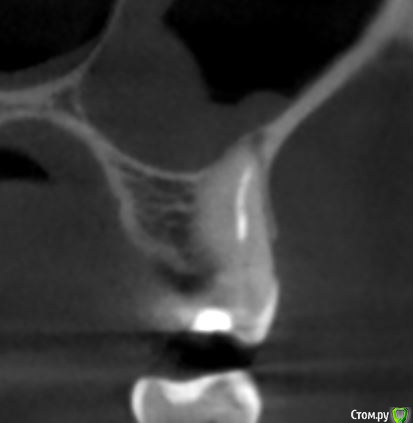

krokomot Опубликовано 19 февраля, 2020 Поделиться Опубликовано 19 февраля, 2020 в медиальном корне недопломбировка и наличие вероятно 4ого канала. Ссылка на комментарий

dmitrib81 Опубликовано 20 февраля, 2020 Автор Поделиться Опубликовано 20 февраля, 2020 Зуб делали много лет назад. Примерно неделю назад появились периодические боли, бывает целый день не болит, потом снова ноющая боль. С приёмом пищи никак не связано. На горячие и холод реакции нетПодскажите, может ещё прислать фоток из КТ Пикассо, а то я в этом ничего не понимаю, просто разных фото экрана прислал, без какого-либо понимания, на что смотреть.. Ссылка на комментарий